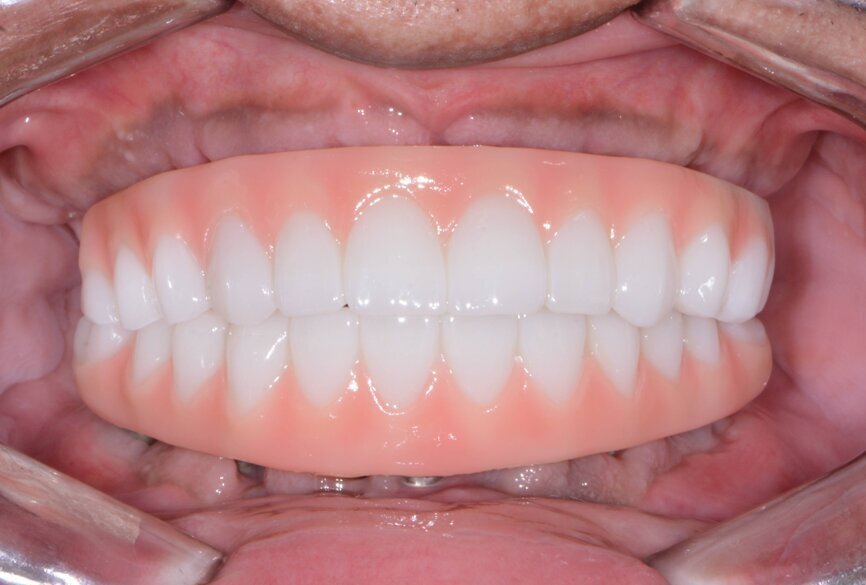

19: Maxillary and mandibular fixed provisional restorations.

Seven days postoperatively, the patient returned with very little discomfort, swelling and bruising. He was very pleased with his new maxillary and mandibular fixed provisional restorations (Figs. 19 & 20). With the patient no longer anaesthetised, the occlusion was checked again to confirm there were no interferences in lateral and protrusive movements. The next step in his treatment would consist of full-arch impressions for the definitive restorations approximately four to five months postoperatively.